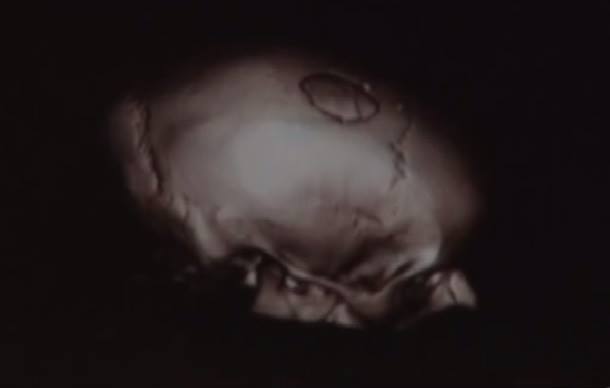

А вот жертвам побоища пришлось провести долгое время в больнице. Они стали инвалидами и потеряли работу. Жена нападавшего в следствие открытого пролома черепа Татьяна похудела на 20 килограммов, сейчас у нее начались проблемы со зрением, слухом и памятью. А у дочери Юлии были две открытые черепно-мозговые травмы и осколочный перелом свода черепа. Теперь у нее бессонница и головокружения. С такими открытыми ранами в голове ей нельзя даже выходить на улицу.

Татьяне и Юлии крайне необходимо поставить титановые пластины. Стоимость операций — порядка 3 тысяч долларов. В семье таких денег нет. Если у вас есть возможность помочь, средства можно перевести на карточку ПриватБанка 4149 4978 4961 4146, Юлия Игоревна Рыбак.